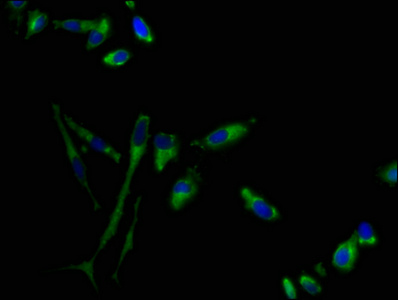

Immunofluorescence staining of Hela cells with CSB-PA009728LA01HU at 1:100, counter-stained with DAPI. The cells were fixed in 4% formaldehyde, permeabilized using 0.2% Triton X-100 and blocked in 10% normal Goat Serum. The cells were then incubated with the antibody overnight at 4°C. The secondary antibody was Alexa Fluor 488-congugated AffiniPure Goat Anti-Rabbit IgG(H+L).